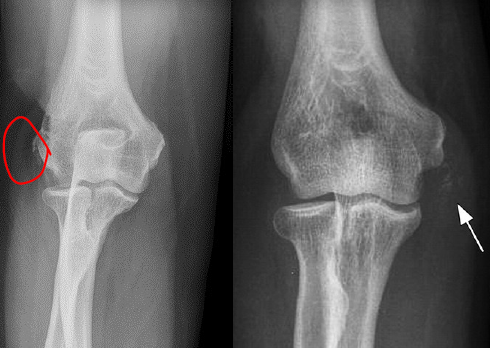

¿Cómo se ve el codo de tenista/golfista en Rx?

Aumento densidad y volumen en epicóndilo medial o lateral

Calcificación –> crónico

Q

¿Cómo se ve el codo de tenista/golfista en US?

• Muy útil

• Tendón engrosado, hipoecogénico

• Rotura